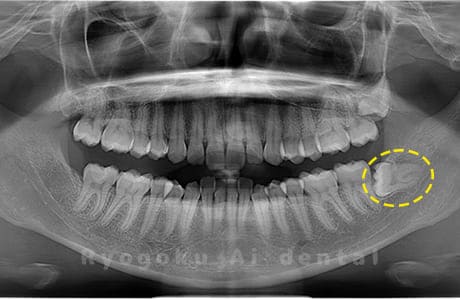

Case01

- 原因

- 水平埋伏智歯

- 治療内容

- 下顎の水平埋伏智歯を抜歯

<リスク・副作用>

手術後は痛み、腫れ、痺れなどの副作用が生じる場合があります。